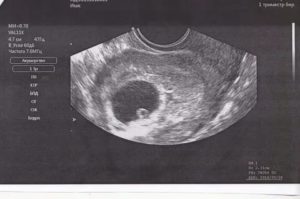

В первые недели развития эмбриона имеет смысл выполнять только трансвагинальное УЗИ.

Это обследование предполагает, что датчик вытянутой формы небольшого диаметра вводят во влагалище женщины и получают с его помощью изображение матки на мониторе аппарата.

В связи с тем, что датчик максимально приближен к изучаемой зоне, тонность исследования очень высокая. Специфической подготовки такое УЗИ не требует. Оно безопасно и не приносит осложнений.

Трансвагинальная методика предполагает введение во влагалище беременной женщины специального датчика, на который надевают презерватив. К 5 акушерской (3 гестационной) неделе вынашивания ребенка уже сформированы желточный мешок, который обеспечивает кроветворную функцию и питание эмбриона и амнион (амниотический пузырек с эмбрионом внутри). На УЗИ можно их отчетливо увидеть на данном сроке.

Наиболее точный вариант исследования, применяемый именно на ранних сроках беременности. Чтобы провести процедуру, на датчик аппарата одевают презерватив и вводят его во влагалище женщины. Уже с третьей недели (от дня зачатия), то есть, на 3-5 день задержки опытный доктор при помощи современного сканера УЗИ сможет зафиксировать факт вашей беременности.

- Трансвагинальное УЗИ – беременность подтверждается в процессе исследования с использованием специального датчика, на который надевают презерватив для УЗИ и вводят во влагалище. Этот метод является наиболее точным и применяется для самой ранней диагностики. УЗИ показывает беременность уже к 21-22 дням от зачатия.